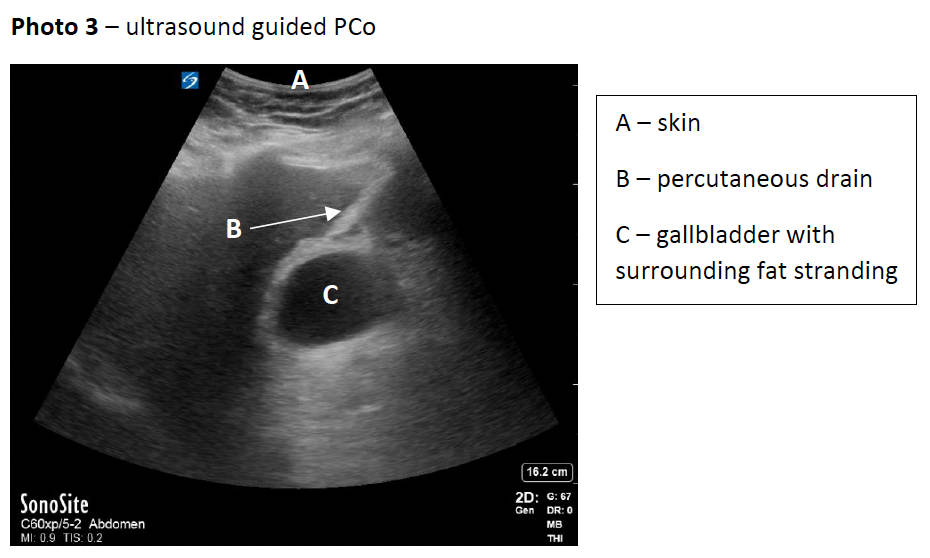

Despite only having ceased clopidogrel for 2 days, due the patient’s deteriorating clinical situation and lack of other options, PCo was performed under ultrasound guidance following a transhepatic approach (photo 3); the position was confirmed using fluoroscopy (photo 4), followed by a 12-French pigtail catheter insertion. Aspirated bile was sent for microscopy/culture/sensitivity which revealed gram-negative rods found to be Klebsiella pneumoniae sensitive to ceftriaxone.